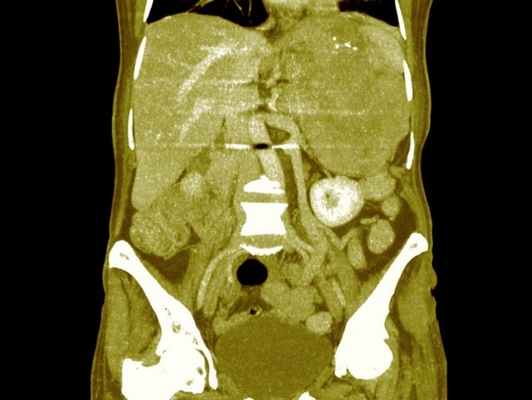

В настоящее время широко используется УЗИ, КТ или МР-томография для выявления расположения опухоли надпочечника, наличия метастазов.

Для обнаружения первичной опухоли, оценки поражения лимфатических узлов, выявления метастазов назначают ультразвуковое исследование почек и надпочечников, других органов, КТ или МРТ с контрастом, рентгенографию органов грудной клетки, сцинтиграфию.

При подозрении на рак надпочечников для исключения метастазов опухоли проводятся компьютерная томография легких и брюшной полости, магнитно-резонансная томография головного мозга. Исследуется компьютерный фенотип опухоли. Цитоплазма клеток аденом и миелолипом надпочечника характеризуется высоким содержанием липидов в отличие от зрелых опухолей. Это свойство используется при денситометрии опухоли. Оценивается плотность жировых и нежировых структур в неконтрастную фазу. Нативная плотность образования менее 10 HU характерна для доброкачественных аденом, альдостером, липом, кист, гематом, абсцессов. Повышение плотности более 10 HU возможно при адренокортикальном раке, феохромоцитоме, метастазах, нейрогенных опухолях, лимфомах. При исследовании плотности на разных фазах выведения контрастного вещества аденомы быстро снижают показатели плотности, злокачественные опухоли имеют тенденцию к задержке контрастного вещества. Разделительная точка – вымывание 50% контраста за 10 минут.